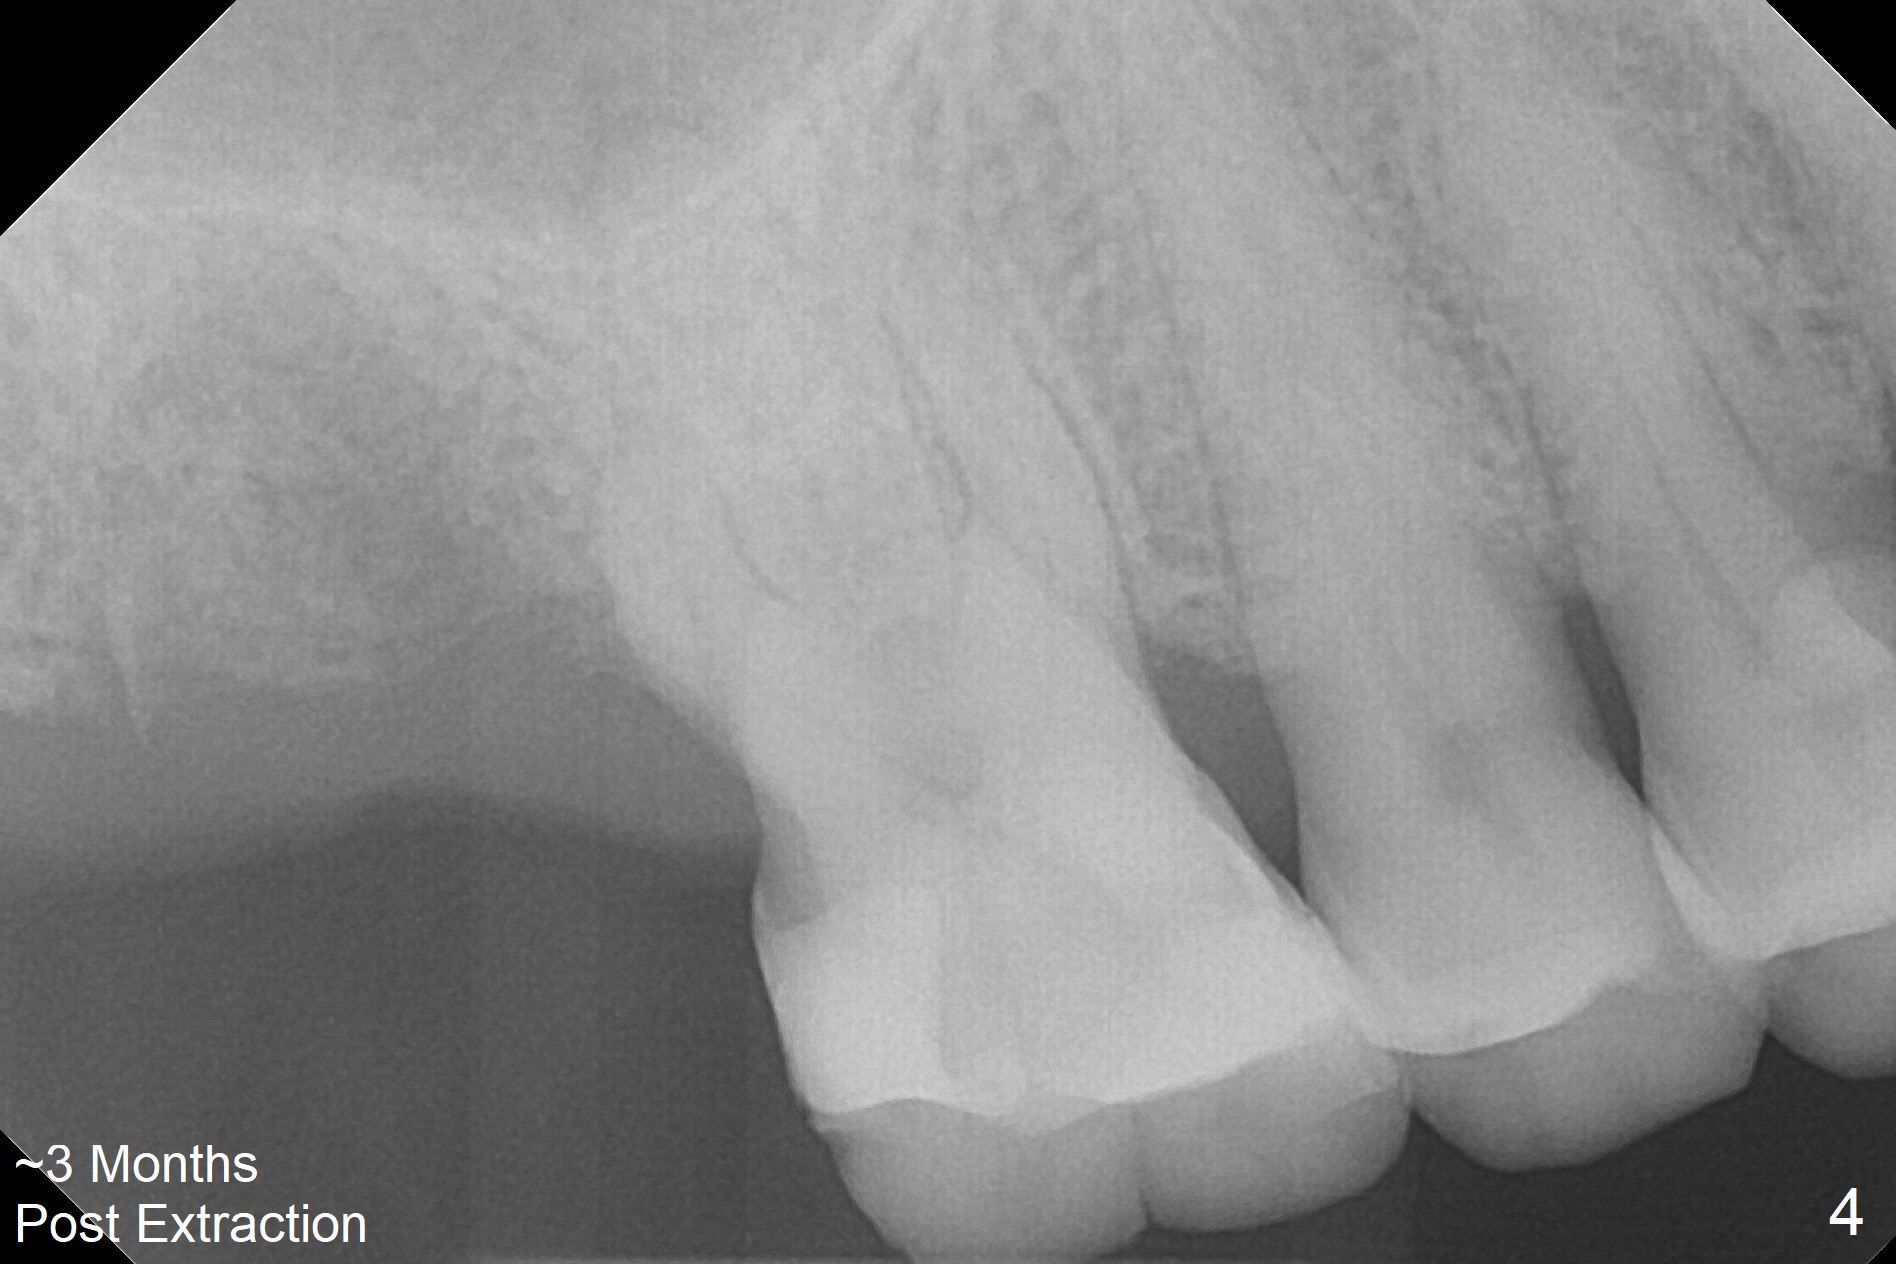

A 65-year-old man returned to finish LR and LL quadrant SRP a few weeks post SRP for UR quadrant and #2 extraction (Fig.1-2). He returns for UL SRP tomorrow ~ 3 months post extraction (Fig.4). Although the patient cannot remember whether socket preservation is done or not, there appears to be bone graft in the socket. The ridge is wide. It seems reasonable to expand and condense the socket using Magic Split and Expanders (flapless). If the patient cannot tolerate tapping, use DIO Bone Expanders. A 6.5x9 (3) mm Magicore will be placed (Fig.5,6).